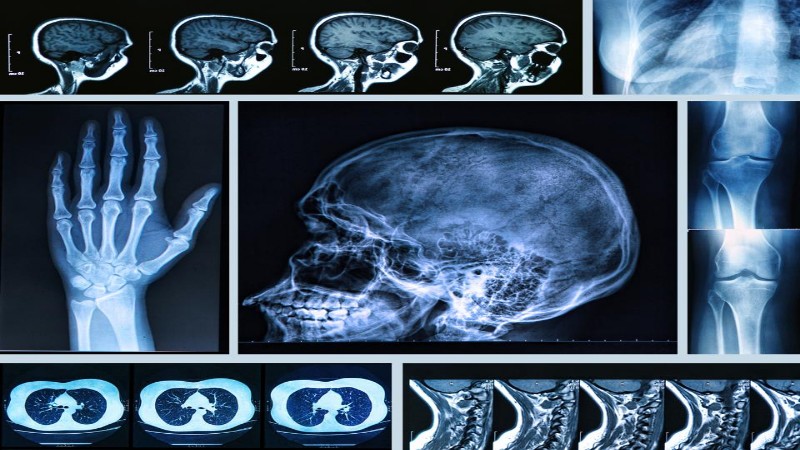

নিউক্লিয়ার মেডিসিন ইমেজিং

চিকিৎসা বিজ্ঞানের রেডিওলজি বিভাগের একটি গুরুত্বপূর্ণ রোগনির্ণয় পদ্ধতি হল নিউক্লিয়ার মেডিসিন ইমেজিং (Nuclear Medicine Imaging)। রেডিওলজি শাখার অন্যান্য রোগনির্ণয় পদ্ধতি যেমন সি টি স্ক্যান, এম… আরও পড়ুন

আলট্রাসোনোগ্রাফি ।। ইউএসজি ।। USG

আল্ট্রাসোনোগ্রাফি বা ইউএসজি একটি মেডিক্যাল ইমেজিং পদ্ধতি যেখানে অত্যন্ত উচ্চ কম্পাঙ্কবিশিষ্ট শব্দ তরঙ্গ ব্যবহারের মাধ্যমে শরীরের মধ্যে থাকা বিভিন্ন অঙ্গ প্রত্যঙ্গ ও টিস্যুর হাই রেজল্যুশন… আরও পড়ুন

এমআরআই ।। ম্যাগনেটিক রেসোনেন্স ইমেজিং ।। MRI Imaging

ম্যাগনেটিক রেসোনেন্স ইমেজিং বা সংক্ষেপে এমআরআই (MRI) এমন একটি অত্যাধুনিক মেডিকেল প্রযুক্তি যার সাহায্যে শরীরের অভ্যন্তরীণ অঙ্গ প্রত্যঙ্গের হাই রেজল্যুশন ছবি তোলা হয়। মূলত চৌম্বক… আরও পড়ুন